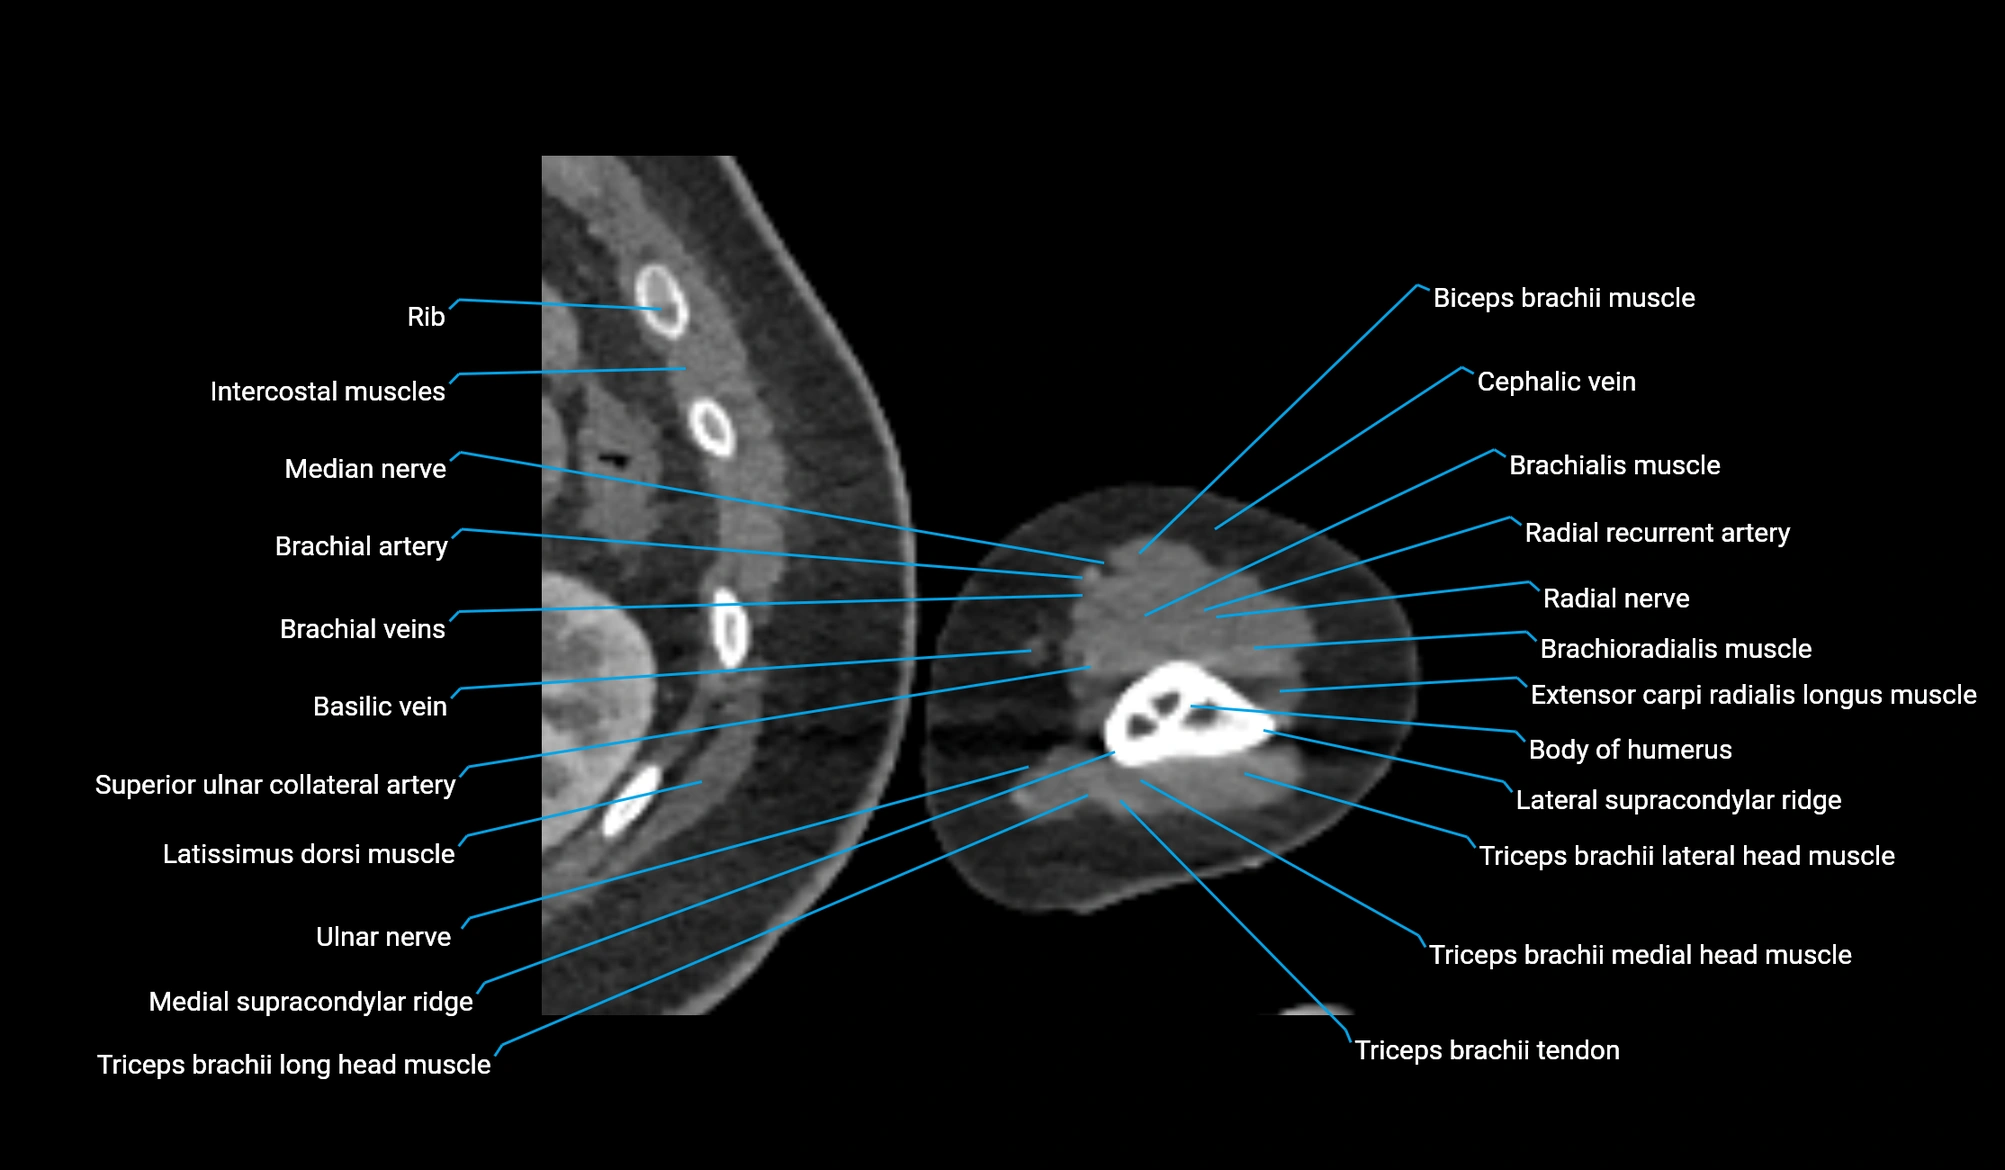

- Body of humerus

- Brachial artery

- Brachialis muscle

- Brachioradialis muscle

- Cephalic vein

- Extensor carpi radialis longus muscle

- Extensor carpi ulnaris muscle

- Flexor carpi ulnaris muscle

- Lateral head of triceps brachii muscle

- Lateral supracondylar ridge

- Long head of triceps brachii muscle

- Medial head of triceps brachii muscle

- Medial supracondylar ridge

- Median nerve

- Radial nerve

- Radial recurrent artery

- Superior ulnar collateral artery

- Triceps brachii muscle

- Triceps brachii tendon